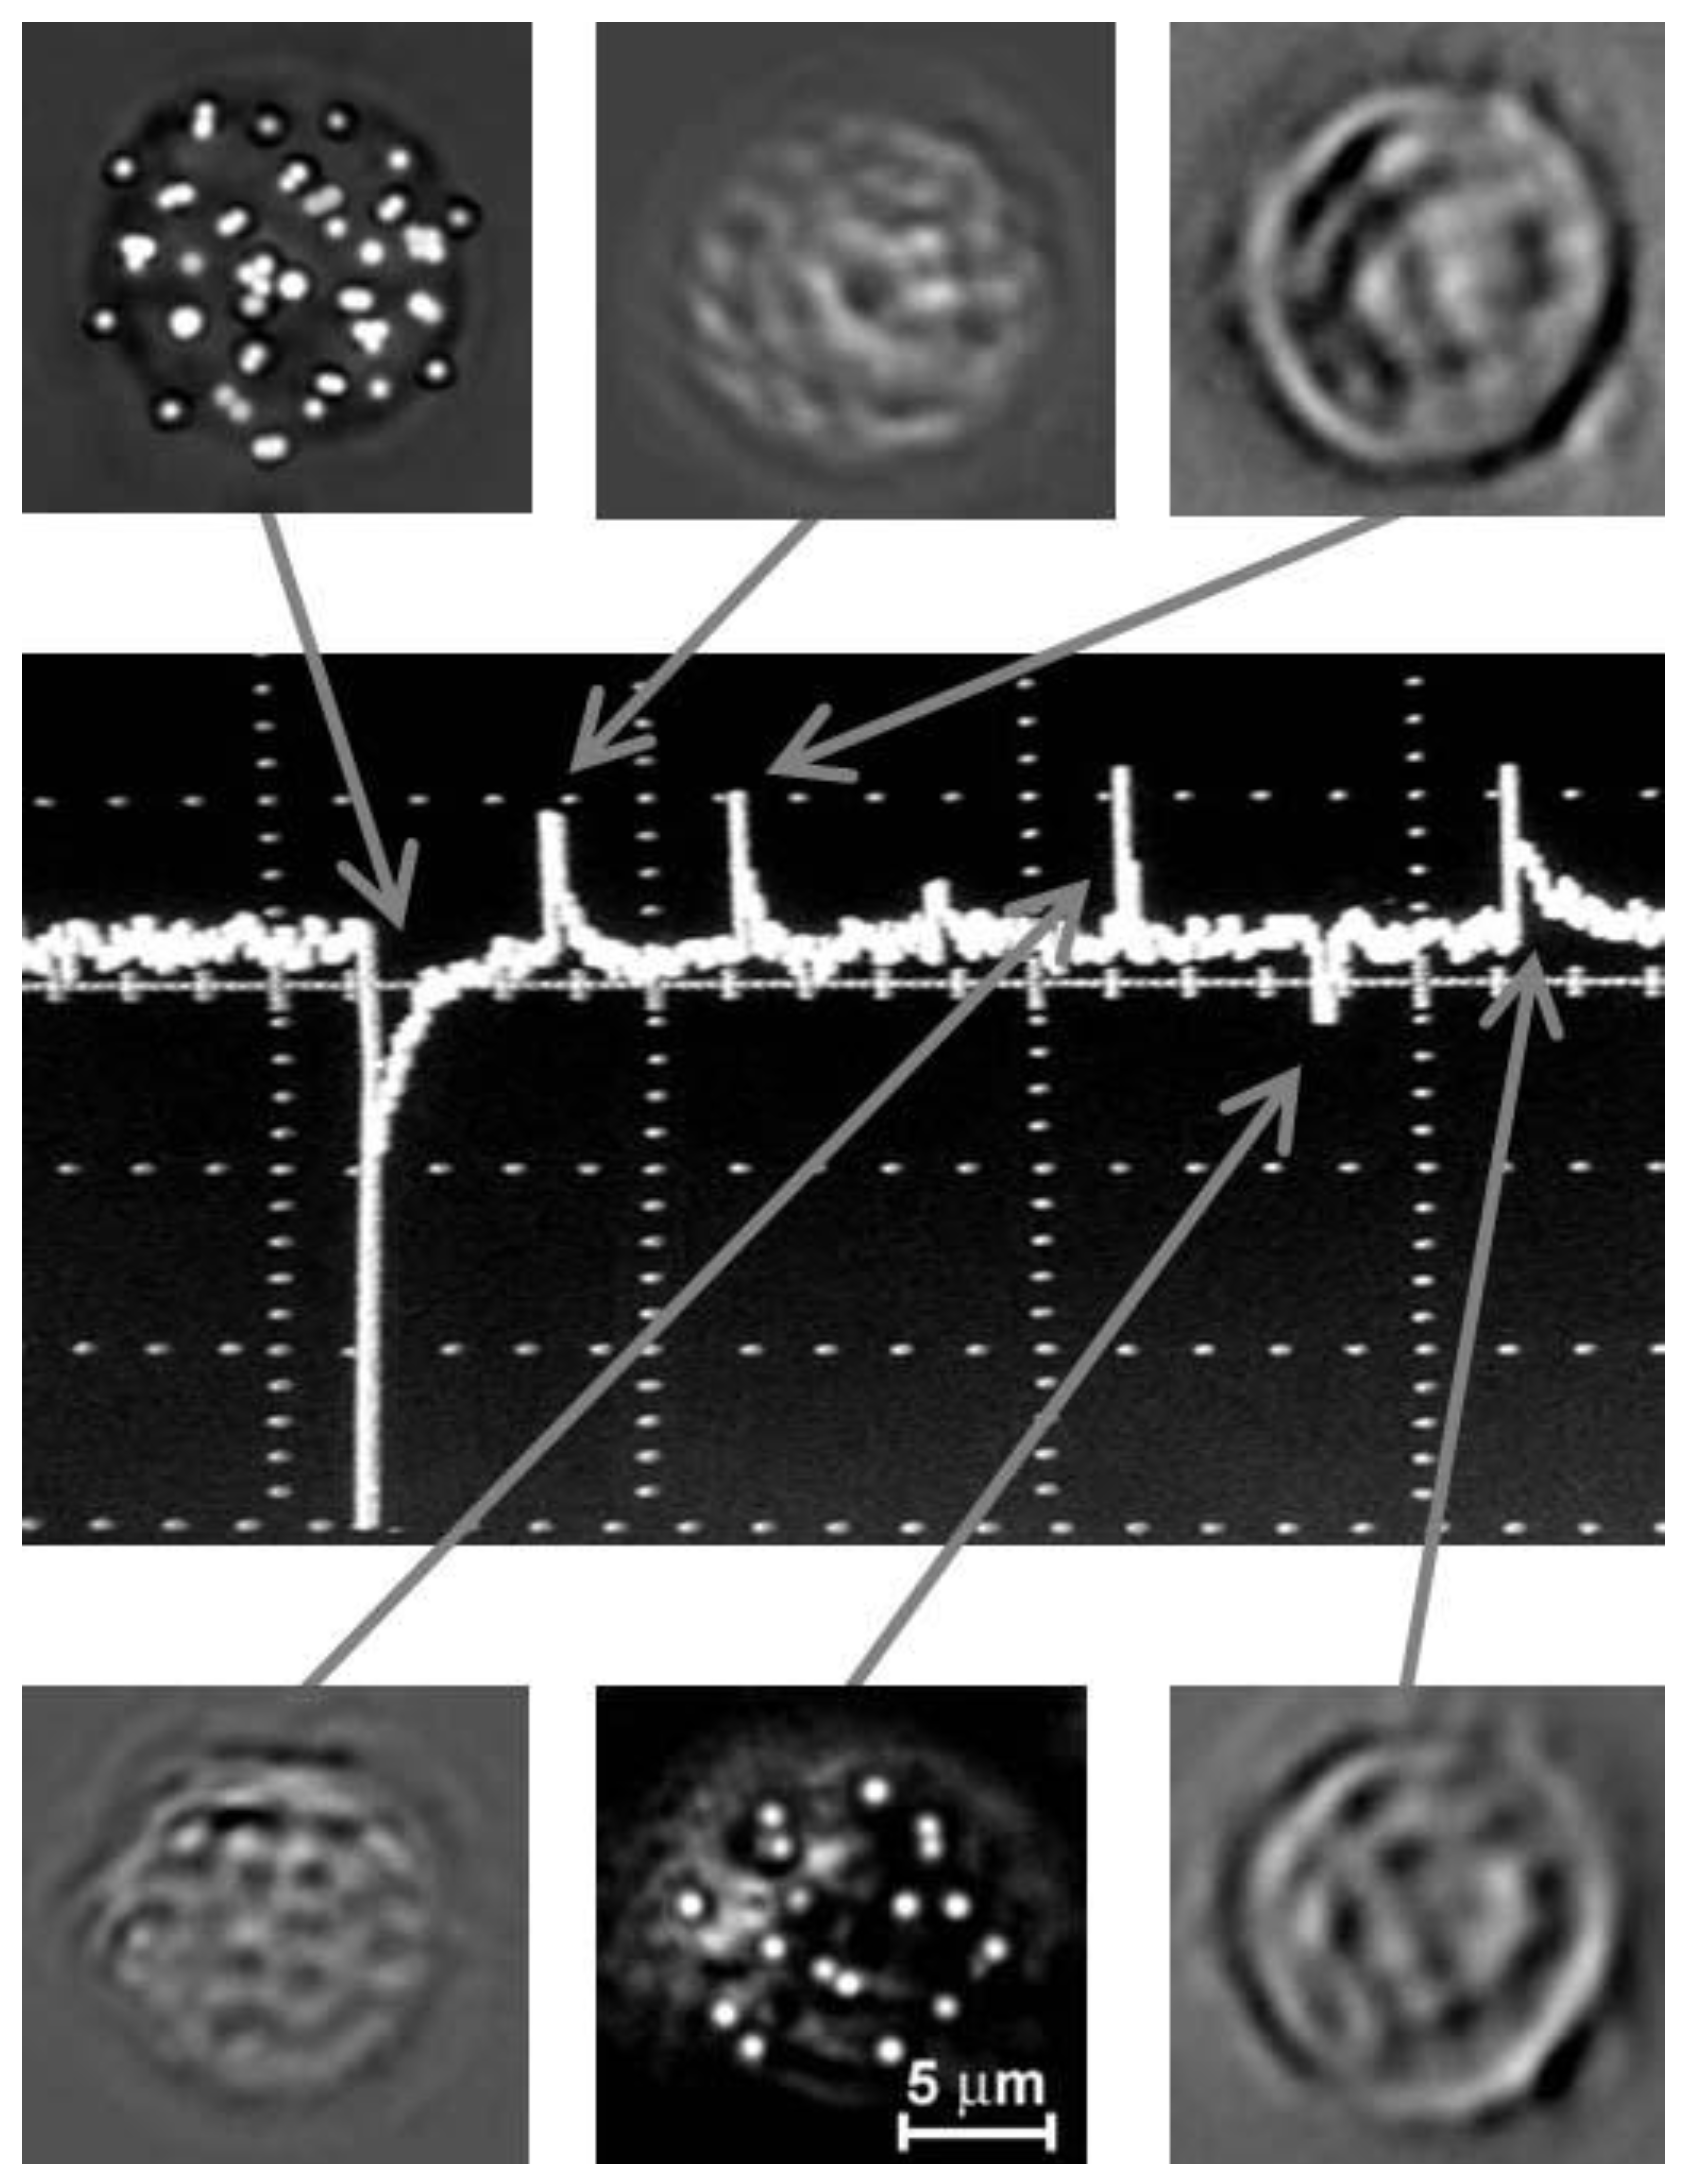

4.8. In Vitro Flow Cytometry Integrating PA, PT and Fluorescence Detection Schematics

- Nedosekin, D.A.; Sarimollaoglu, M.; Galanzha, E.I.; Sawant, R.; Torchilin, V.P.; Verkhusha, V.V.; Ma, J.; Frank, M.H.; Biris, A.S.; Zharov, V.P. Synergy of photoacoustic and fluorescence flow cytometry of circulating cells with negative and positive contrasts. J. Biophotonics 2013, 6, 425–434. [Google Scholar] [CrossRef]